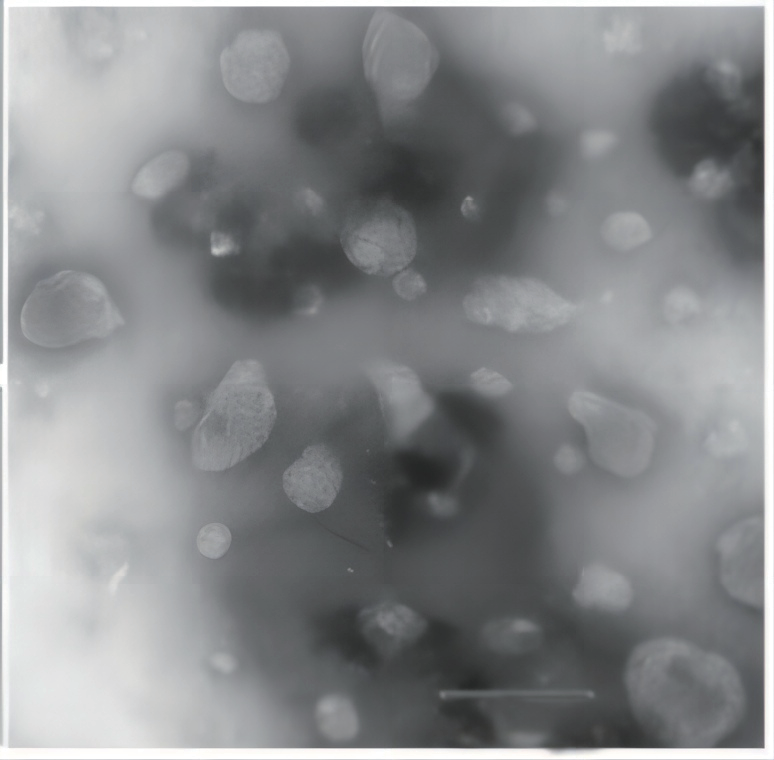

在处理脂质体时监测粒径至关重要,Nicomp3000系列纳米粒度仪经常用于此应用。13-20在Entegris的一项内部研究中,脂质体是使用3:1:1的HSPC、胆固醇和mPEG-DSP的配方制成的。样品首先通过转速7200rpm混合10分钟,然后使用微射流均质机21搭配Y型腔采用25000psi的压力制成脂质体。对样品进行均质处理1次、3次、5次和10次,使其通过微流器。预混物和处理过的样品的图像(从左到右)如图7所示。

图7. 预混合,均质1次、3次、5次和10次